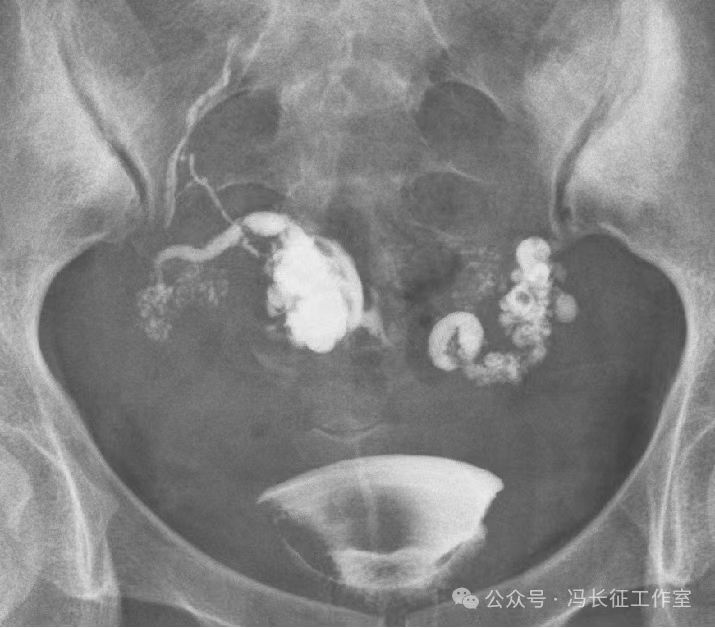

输卵管积水的子宫输卵管造影尽量包括这5个方面的描述,诊断的临床意义才最大,这样才能给好的生殖科医生有价值的建议,帮助给不孕者制定最好的助孕治疗方案。比如这例输卵管积水,峡部结节性输卵管炎(病因),交通性(积水近端是否和宫腔相通),中度(积水大小),厚壁(管壁的厚度),多囊(囊腔的多少)。

微信图片_20240220111130(2).jpg

最后诊断应该是:双侧峡部结节性输卵管炎并双侧中度、厚壁、多囊、交通性输卵管积水。